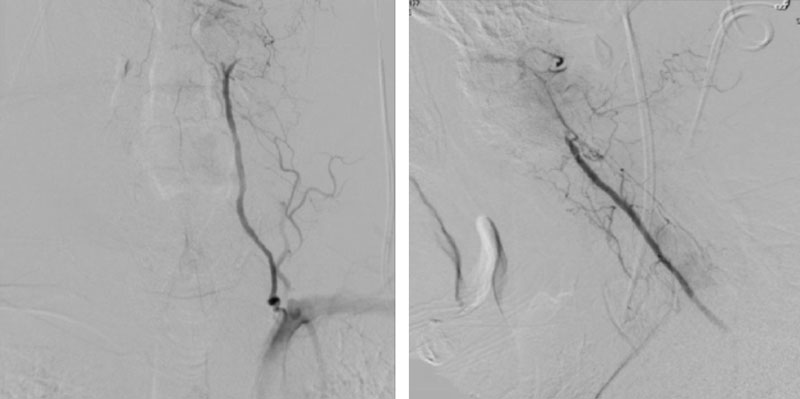

The patient was brought to the operating room, and general tracheal anesthesia was initiated via fiberoptic approach. Somatosensory potentials, motor evoked potentials, and brainstem auditory evoked responses were recorded. The patient then underwent intraoperative angiography of the right Vertebral Artery performed via a 5 French Right Radial Artery access. Once it was established that he had good flow, a Mayfield head holder was attached to the patient’s head on the 60 pounds of torque pressure. The Wilson frame attached to the Jackson table was then placed on top the patient attached to the Jackson frame. The patient was secured with straps and bed sheets and then positioned prone by rotating the frame around its axis. The flat plate of the Jackson table was then removed, and the patient bony prominences and soft tissues were adequately padded. Angiography was then again repeated showing good flow through the Vertebral Artery. After that, after being properly secured to the table with access to the right radial sheath, the neck and the left posterior iliac crest area and a tricortical autograft was then obtained with osteotomes. Iliac crest was reconstructed with fiber graft allograft. Posterior cervical incision was then performed and the spinous processes of C2 and C3 were identified and cleared of the fascia and then the muscle the way to the lateral edges of lateral masses. The C1 posterior ring was completely subluxed under the occiput and C2 lamina. The patient evoked potentials remained stable. The C1 lamina was then cleared of the soft tissue laterally on both sides. On the left side, significant osteophyte formation was visualized, and the C1-2 foramen was completely closed by the bone. On the right side, the C1-2 foramen was dissected, and the veins were coagulated with bipolar cautery. The C2 nerve root was identified and then coagulated bipolar cautery and divided with micro scissors, completing the planned C2 rhizotomy. The decision was made to perform an occiput to C3 fusion, since the articulation between the occiput, C1, and C2 was technically difficult and most likely would result in an inadequate fixation. At that point, a small occipital plate was brought into the field, and secured to the suboccipital bone with 14- and 12-mm screws. Then a pilot hold was created into the lateral masses of C3 bilaterally. The C3 appeared to be solidly fused to C2. First a hole was made with the drill and then passes were made with 40 mm drill with the guide. There were palpated with a ball-tipped probe and tapped. After the replaced 14 mm lateral mass screws into the lateral masses of C3 bilaterally. After the rods were fashioned and secured to the screw heads and the occipital plate with locking caps. (Figure 6)

Intraoperative angiography was then repeated again, showing good flow through the right Vertebral Artery into the Basilar Artery. Intraoperative fluoroscopy was then also performed to confirm good position of the screws and rods in both AP and lateral projections. (Figure 7)

After a diagnosis is confirmed, several options including conservative approaches (cervical collar) or surgical approaches can be considered. Surgical therapy must be tailored to the source of occlusion and may include fascial decompression, osteophyte removal and unroofing of the foramina, or in cases of subluxation and instability – surgical fusion. As described in our patient, the level of occlusion occurred at the Occiput-C1/C2 level secondary to subluxation of C1 at the level of the Foramen Magnum which necessitated cervical fusion. In the absence of his contralateral left Vertebral Artery, avoiding direct surgical manipulation and potential damage to his dominant/isolated Right Vertebral Artery supply, necessitated extreme care during his surgical fusion and instrumentation to avoid the course of the vessel thru the lateral masses of C2 and intraoperative angiography during the critical stages of his fixation (supine post intubation, rotational proning, and prior to final fixation of his instrumentation).7,8